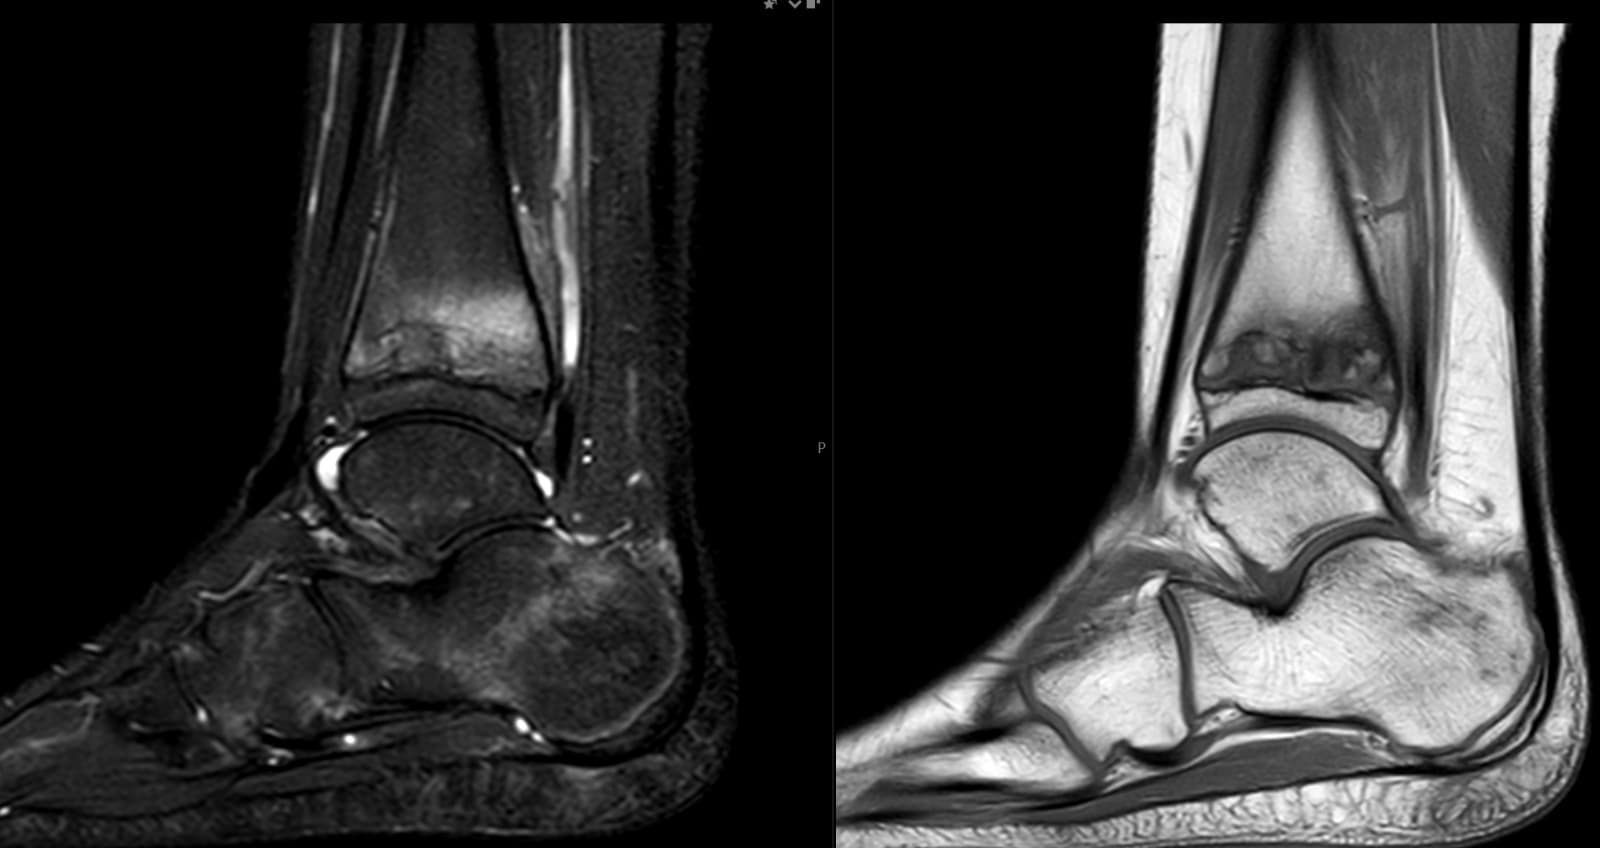

Eksempler fra reelle MSK-kontekster, herunder skulder, knæ, ankel og håndled, hvor strukturerede second opinions ofte giver størst klinisk værdi.

Komplekse skader, smerter, instabilitet, sene/ligament‑patologi, marvabnormiteter og postoperative tilfælde.